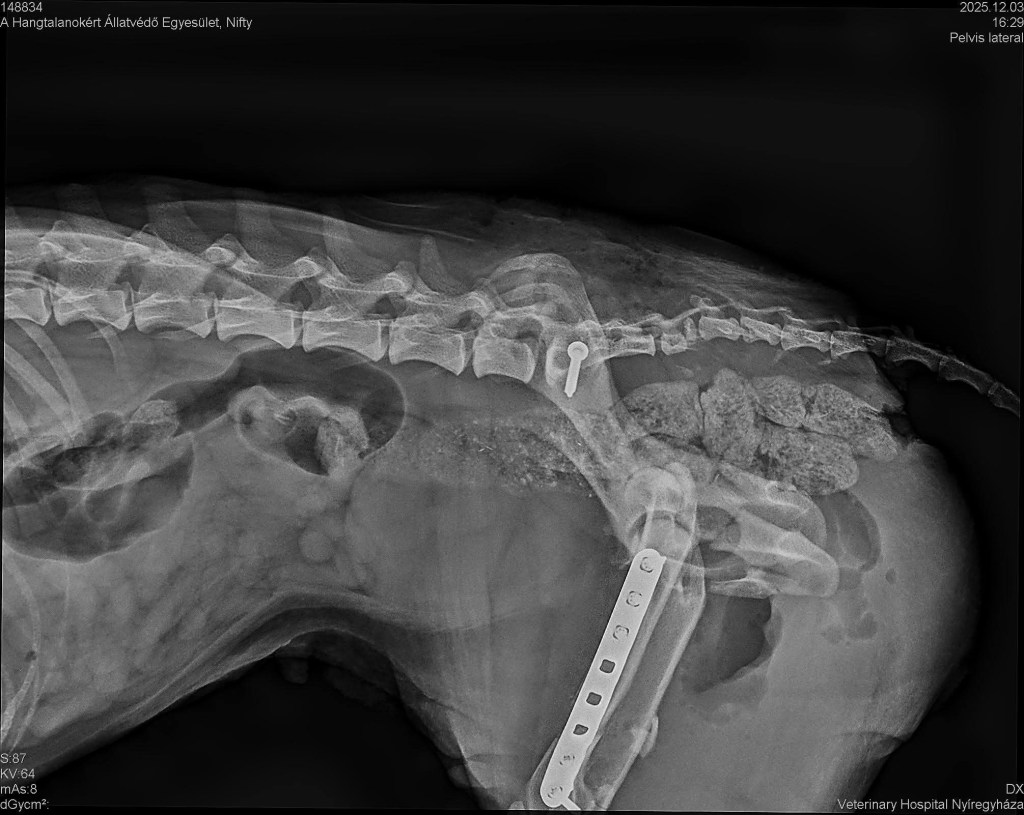

Den Röntgenbildern ist zu entnehmen, dass mehrere Brüdhe (Schienbein, Oberschenkelknochen, angebrochenes Becken) behoben wurden. Stunden vergingen, doch die tapfere Mausi hat sich gut geschlagen. ![]()

Jetzt darf sie sich im Inneren des Tierheims ausruhen und bekommt die Hilfe, die ihr zusteht. Zum Glück wurde kein Nerv beschädigt, Nifty kann sich eigenständig entleeren und ihre Wirbel wurden wieder eingerenkt.